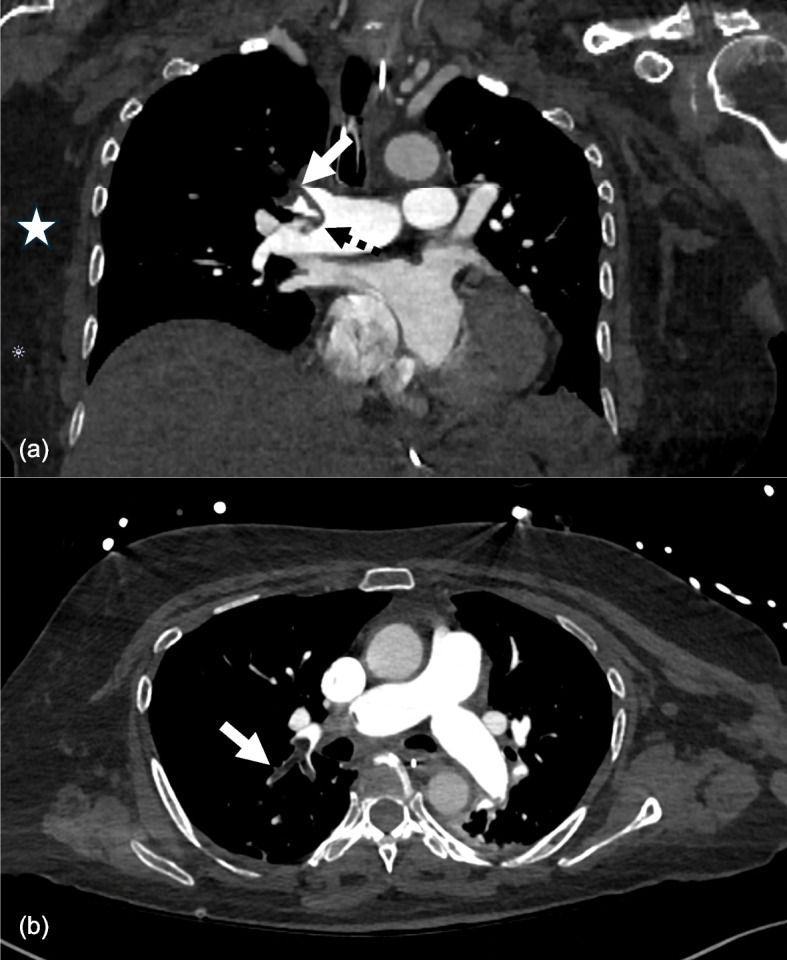

Case presentation: We present a case report of a 73-year-old woman with macroscopic fat pulmonary embolism after a neck of femur fracture. Initially, she had severe circulatory shock, requiring multiple vasopressors and admission to the Intensive Care Unit. A percutaneous large-bore mechanical thrombectomy was performed, after which notable improvements to haemodynamic function and overall clinical trajectory were observed.